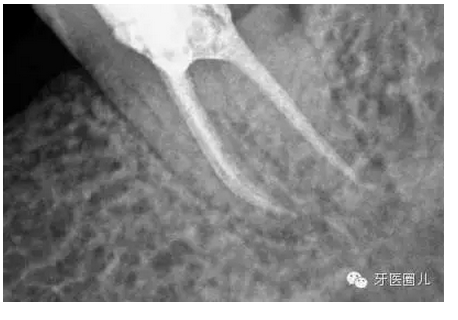

這三個(gè)病例采用protaper器械,最后一個(gè)病例有不足,遠(yuǎn)中舌根根尖2mm有一個(gè)嚴(yán)重的向上彎曲,預(yù)備和充填時(shí)沒有到達(dá),術(shù)前評(píng)估和術(shù)中評(píng)估時(shí)覺得這個(gè)病例難度超過(guò)了我的操作范圍,但是患者沒有精力選擇更好的醫(yī)院,我于是和他講明狀況盡量做到我能做的了